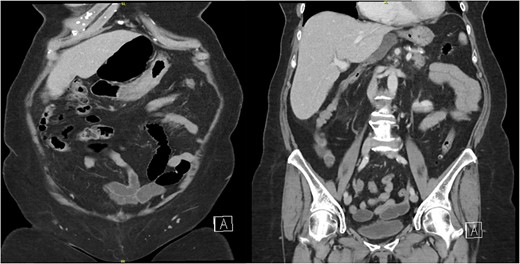

The patient’s laboratory values were significant for WBC 12.2 × 109/L, potassium 3.1 mmol/L, creatinine 0.59 mg/dl, lipase 676 U/L, total bilirubin 1.8 mg/dl, direct bilirubin of 0.6 mg/dL, ALT/AST 147/221 U/L, and alkaline phosphatase of 579 U/L. A computed tomography (CT) scan of the abdomen and pelvis with intravenous contrast demonstrated the cecum herniating through the foramen of Winslow with no signs of ischemia or bowel obstruction (Fig. 1); the gallbladder was distended with pericholecystic stranding and surrounding portal triad inflammation (Fig. 2).

Two coronal images from a computed tomography (CT) scan of the abdomen and pelvis with intravenous contrast demonstrating the cecum herniating through the foramen of Winslow with no signs of ischemia or bowel obstruction.